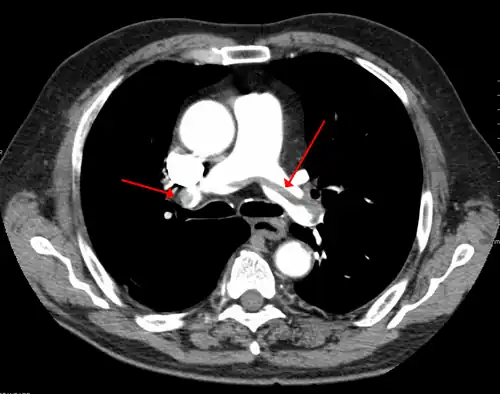

A pulmonary embolism (PE) occurs when a blood clot from a deep vein (a DVT) detaches from a vein (embolizes), travels through the right side of the heart, and becomes lodged as an embolus in a pulmonary artery that supplies deoxygenated blood to the lungs for oxygenation.[28] Up to one-fourth of PE cases are thought to result in sudden death.[12] When not fatal, PE can cause symptoms such as sudden onset shortness of breath or chest pain, coughing up blood (hemoptysis), and fainting (syncope).[29][30] The chest pain can be pleuritic (worsened by deep breaths)[29] and can vary based upon where the embolus is lodged in the lungs. An estimated 30–50% of those with PE have detectable DVT by compression ultrasound.[30]

- A CT image with red arrows indicating PE (grey) in the pulmonary arteries (white)